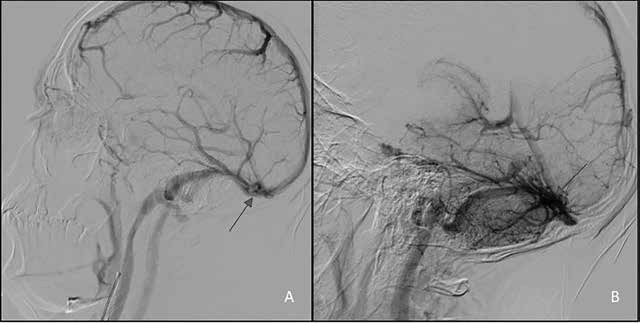

Figura 2. Angiotomografía

computarizada: A) malformación

arteriovenosa dependiente de la circulación de las arterias comunicantes

posteriores; B) nido

vascular de MAV a nivel temporo-occipital

izquierdo

La

angiotomografía computarizada se realizó en cortes axiales

con contraste desde

la base hasta

la convexidad del cráneo. Después de

inyectar contraste se evidenció llenado

adecuado de vasos arteriales y venosos. La circulación anterior

no presenta alteración; sin embargo, en la

circulación posterior se revela hipoplasia de arterias

comunicantes posteriores más ruptura de malformación

arteriovenosa cerebral temporo-occipital con vaso nutricio aislado en

hemisterio cerebral izquierdo (ver Figura 2).